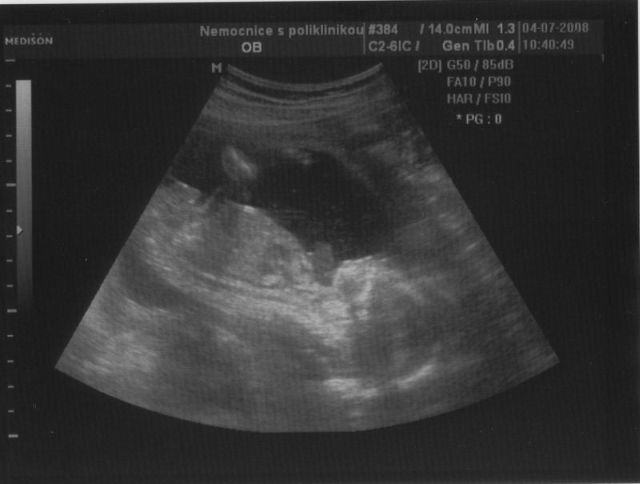

Doktor mi začátkem listopadu 2007 vysadil HA z důvodu zdravotních potíží,dávali jsme si tedy pozor a čekali,zda potíže ustoupí,ale 31.prosince 2007 mi manža řekl,že by chtěl miminko,byla jsem z jeho návrhu vykulená,ale byla to překrásná představa a tak jsem souhlasila..Od 8.ledna 2008 jsme se tedy začali snažit o miminko,začala jsem pít kontryhel a zobat Calibrum babyplan,aby mému tělu nic nechybělo 🙂 Nechávali jsme tomu volný průběh,ani jeden z nás na to nijak nepospíchal,nevím,proč jsem si říkala : Do roka se to snad povede 😀 A 29.3.2008 jsem měla pozitivní testík,sama jsem nechápala,jak brzy se to povedlo 🙂 Byla jsem neskutečně šťastná a stále jsem 🙂 Termín porodu dle MS 5.12.2008 a dle utz ve 12.tt 30.11.2008 Už od začátku jsem tušila,že čekám kluka a tak hned z první kontroly v 5.tt jsem si koupila modré bačkůrky pro štěstí,které se mnou chodili na každou kontrolu 🙂 Od 15.tt mi začalo celkem hodně tvrdnout břicho a chvilkama to bylo velice nepříjemné,na další kontrole,to jsem byla 18+4 , jsem to doktorovi řekla,ten mi pověděl,že se mu to vůbec nelíbí a tak mě poslal na utz,na utz jsem čekala 2 hodiny a můžu říct,že to byli nejhorší 2 hodiny v mém životě,tolik jsem se o miminko bála,ten strach,že něco není v pořádku byl opravdu k nevydržení..Přišla na mě řada a tak jsem tedy šla do kabinky a následně na lehátko na utz,pan doktor konstatoval,že všechno vypadá v pořádku a že se nemám bát,předepsal mi magnezium a že by to mělo pomoct,navíc koukám na ten utz a povídám panu doktorovi,to co tam vidím jsou kouličky? 😀 A on že jistě,že si myslel,že už to dávno vim,když se tak krásně ukazuje 😀 ,můj doktor mi řekl,že zřejmě porodím předčasně,což mě celkem vyvedlo z míry..Ale jsem optimisticky naladěnej človíček a tak jsem Honzíkovi vysvětlovala,že v bříšku musí ještě zůstat..Ve 20.tt jsem šla na velkej UTZ,kde mi opravdu řekli,že Honzík je zdravej a opět Honzík ukázal,že je 100% chlapeček 😀 Ve 26.tt jsme jeli na 4D utz do Liberce,tam se Honzík ukázal zas,no za celé těhu se nestalo,že by se na utz neukázal aa neroztáhl nožičky,máme malýho exibouše 😀 Ve 30.tt mě čekal další UTZ,vše v pořádku,Honzík už byl hlavičkou dolů a vážil 1600g ..Ve 35.tt mě doktor opět kvůli tvrdnutí břicha poslal už do ambulance,aby se o mě starali už tam.. Ten den jsem strávila v nemocnici 7hodin,fakt děsný !!! 2 hodiny čekání u mého doktora,ten mě tedy poslal už do nemocnice,takže jsem musela na UTZ,tam jsem čekala 2 hodiny,pak na natáčky,tam jsem čekala hodinu a pak na ambulanci a tak jsem čekala zas dvě hodiny ☹ Na UTZ ve 36.tt měl Honzík už 2600g ..